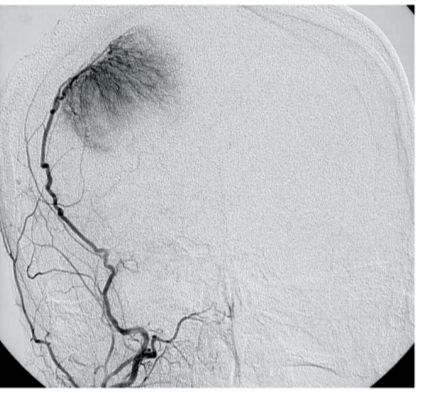

40 70 歳の女性。けいれんのため搬入された。意識レベルは JCSⅡ- 10。体温 36.8 ℃。脈拍 98/分、整。血圧 138/86 mmHg。呼吸数 16/分。SpO2 96 %(room air)。 対光反射と眼球運動とに異常を認めない。左上下肢の不全麻痺を認める。来院時の 頭部 MRI の FLAIR 像(別冊No. 1A)と塞栓術のために施行した外頸動脈造影の写 真(別冊No. 1B)とを別に示す。 診断として考えられるのはどれか。 (A) 髄膜腫 (B) 胚細胞腫 (C) 神経膠腫 (D) 悪性リンパ腫 (E)転移性脳腫瘍